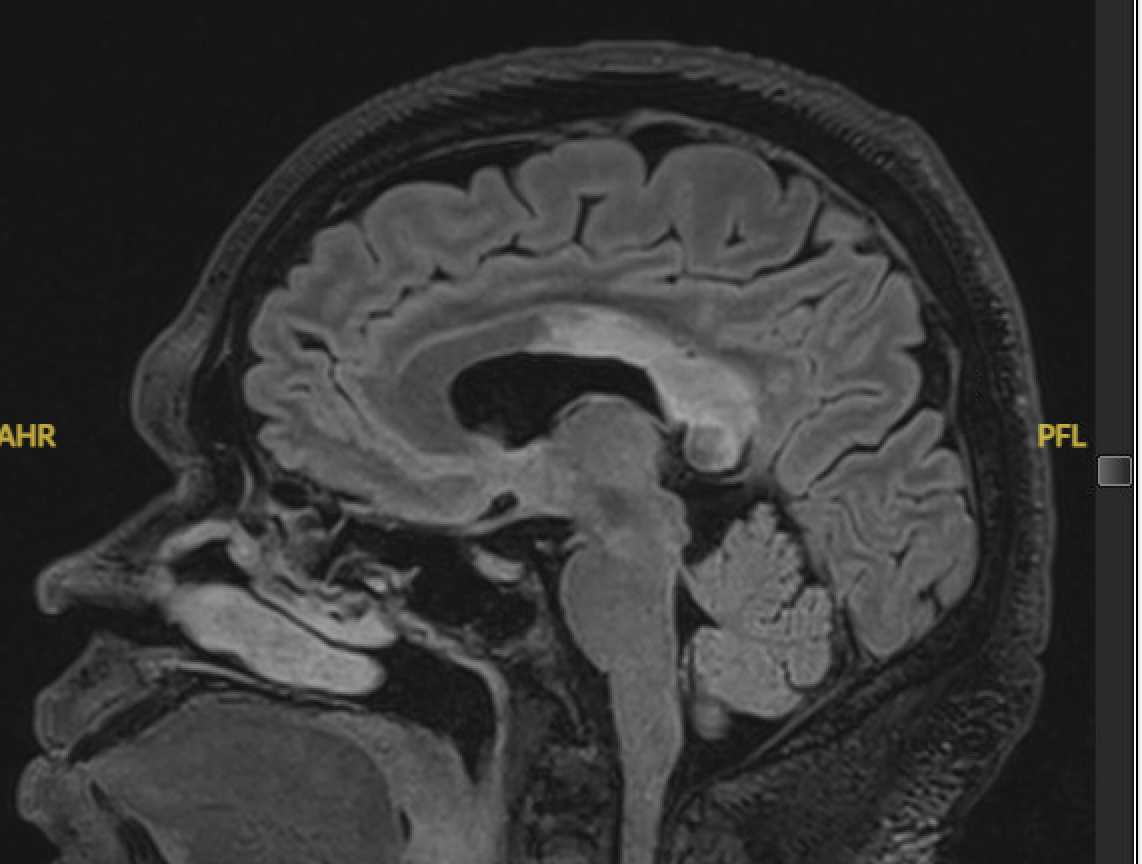

Although this wasn’t a classic neurologic deficit, we proceeded with an urgent CT/CTA, which revealed an isolated infarction of the corpus callosum. (See CT and then T2 FLAIR MRIs)

T2 FLAIR MRI SAG